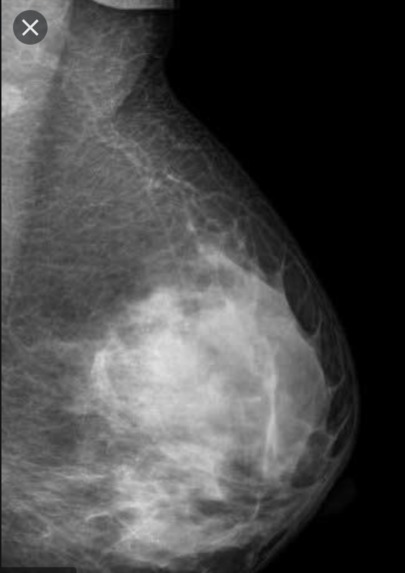

RoboDoc is a messenger bot where people could chat with it and get their symptoms analyzed using messages. Based on symptoms sent by the user it analysis and most accurate diseases are diagnosed. At present we have added 21 common diseases we will be expanding it to 87 diseases our main objective was to lessen the panic caused by the coronavirus pandemic. We have added analysis of Frontal chest x-ray for covid19 and analysis of mammography for breast cancer detection.

For the COVID19 detection model using X-rays, we used Kaggle and Github dataset accounting for total of 1300 COVID19 and 1200 normal chest x-rays. For breast cancer, we used the Kaggle dataset. For symptoms and disease, we used a CSV file for NLP training.

We are using wit.ai for Natural Language Processing and based on symptoms mentioned by users we are predicting the disease and for detection of covid19 using chest x-ray and breast cancer using mammography we are using tensorflow.js models and javascript